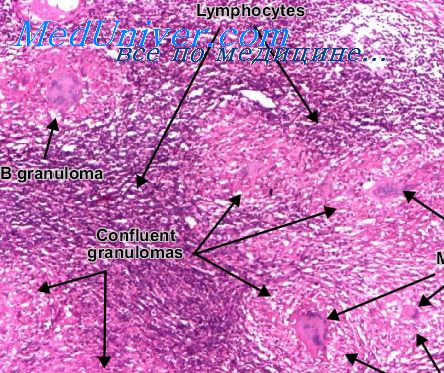

Микроскопический взгляд на мишитарный туберкулез легкого: фотодокументация

Раздел: Снимки-откровения